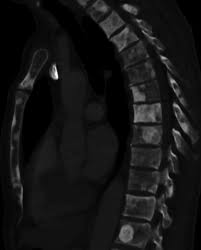

Metastatic Spine Tumors

Metastatic Spine Tumors from embed.widencdn.net